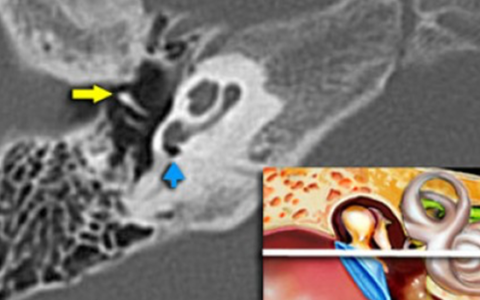

КТ анатомия сосцевидного отростка: особенности и показания